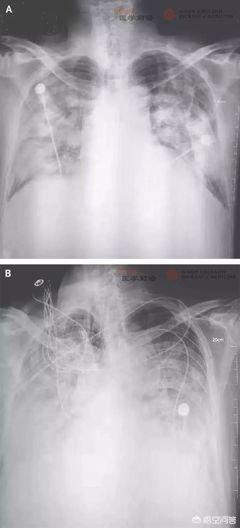

発熱、倦怠感、咳嗽、呼吸困難はない。画像所見:初期には多発性の小斑点状陰影と間質性変化を呈し、肺の外帯は明らかである。その後、両肺に多発する研削ガラス影や浸潤影に発展し、重症例では固形肺変化が出現することもあるが、胸水貯留はまれである。採血とその他の臨床検査:末梢血白血球総数は正常か、あるいは病初期には減少し、リンパ球数は減少し、肝酵素、筋酵素、ミオグロビンは一部の患者で増加する。C反応性蛋白(CRP)と血沈はほとんどの患者で上昇し、カルシトニノーゲンは正常である。重症例では、Dダイマーが上昇し、末梢血リンパ球が徐々に減少する。新型コロナウイルスの核酸は、咽頭ぬぐい液、喀痰、下気道分泌物、血液などの検体から検出されます。

新型コロナウイルス肺炎の症状が非典型的であれば、誤診されるのではないかという疑問をお持ちの方もいらっしゃるでしょう。このような可能性があるため、臨床症状だけで診断を下すことはできない。では、どうすればいいのか?この時、疫学的な病歴に頼る必要があり、発症前14日間に、新型コロナウイルス肺炎の流行地域に行ったことがあるか、あるいは感染地域の人と接触したことがあるか、あるいは周囲の人と密接に接触したことがあるか、あるいは罹患者の集まりがある場合、さらに新型コロナウイルス肺炎の感染かどうかを明らかにする必要があり、血液ルーチン、胸部X線写真を見直す必要があり、血液ルーチンで白血球やリンパ球が減少していることが示唆される場合、胸部X線写真で、帯状の外側の肺に複数の小さな斑点があること、あるいは両肺に複数の地硝子影があることが示唆されます。血液検査で白血球増加やリンパ球減少がみられ、胸部レントゲン写真で肺の外側の帯状に小さな斑状の影が多発したり、両肺に複数の地硝子影や浸潤影がみられたり、さらには肺に固形病変がみられたりする場合は、新型コロナウイルス感染による肺炎を強く警戒する必要がある。これら3つの疾患の予後については、感冒患者は積極的な治療により予後良好、インフルエンザ患者は高齢者や体力の低下した患者は肺炎を起こしやすく死亡率が高い、新型コロナウイルス感染症患者は肺炎を起こし、その多くは予後良好であるが、高齢者や慢性疾患患者は予後不良である。

新型コロナウイルス肺炎に感染した患者が肺CTを撮影すると、初期段階では明らかに外側の肺の帯に複数の小さな斑状の影と間質性変化を示唆し、その後、複数のグラウンドグラスの影、浸潤影を持つ両側の肺に発展し、深刻なケースでは、肺の固形変化、胸水が表示されることがありますまれです。ルーチン血液検査では、正常または減少の初期段階で末梢血白血球の総数が減少し、リンパ球数が減少し、一部の患者の生化学検査では、肝臓酵素、ミオシナーゼ、ミオグロビンが表示されます。肝酵素、筋酵素、ミオグロビンが増加する患者もいる。 ほとんどの患者で、C反応性蛋白と血沈は上昇し、カルシトニノーゲンは正常で、リンパ球は徐々に減少する。

臨床症状:1.発熱:2.肺における肺炎の画像変化:3.総白血球数の減少または正常値、または経過の初期におけるリンパ球数の減少。